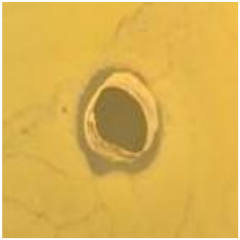

| AgNPs | 11.5 ± 1.7![]() | 10.6 ± 0.6![]() | 8.8 ± 0.5![]() | 8.8 ± 3.0![]() |

| Vancomycin | 22.5 ± 0.5![]() | 22.5 ± 0.5![]() | 8.0 ± 0.1![]() | 8.0 ± 0.2![]() |

| LL37 | 6.5 ± 0.1![]() | 6.5 ± 0.5![]() | 6.3 ± 0.1![]() | 6.2 ± 0.1![]() |

| Pexiganan | 9.0 ± 0.5![]() | 12.2 ± 0.6![]() | 8.0 ± 1.5![]() | 12.0 ± 0.1![]() |

| TTO | 20.2 ± 0.1![]() | 15.0 ± 0.5![]() | 15.5 ± 0.5![]() | 13.3 ± 0.3![]() |

| CLO | 21.5 ± 0.5![]() | 15.0 ± 1.0![]() | 15.0 ± 1.9![]() | 15.0 ± 0.6![]() |

| NO | 14.7 ± 0.4![]() | 10.0 ± 0.5![]() | 11.5 ± 0.5![]() | 6.8 ± 0.5![]() |